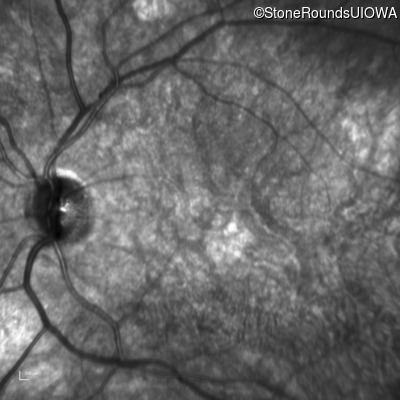

Optical Coherence Tomography - Left - 20/100

Exemplar / OCT Stack

Infrared Fundus Photograph - Left - 20/100

Exemplar